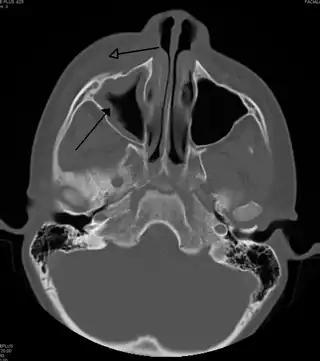

Celulitis periorbitaria secundaria a infección dental (con presencia de sinusitis maxilar)

La celulitis periorbitaria debe diferenciarse principalmente de la celulitis orbitaria, debido a que la segunda requiere un manejo hospitalizado con tratamiento antibiótico endovenoso y, en algunos casos, drenaje quirúrgico. En general, los pacientes con celulitis periorbitaria presentan una lesión eritematosa con bordes difusos, con aumento de la temperatura local, fiebre, dolor e inyección conjuntival con epífora. En contraste con una celulitis orbitaria, no tiene compromiso ocular (indemnidad de los movimientos oculares, ausencia de dolor y sin compromiso de la agudeza visual). En caso de presentarse alguno de estos síntomas, es necesario realizar una tomografía computarizada para descartar compromiso postseptal.[4]